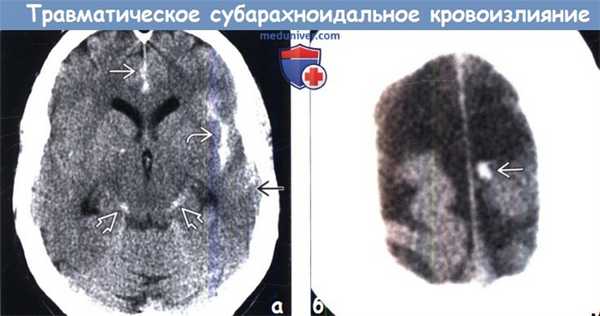

Диагностика травматического субарахноидального кровоизлияние на КТ, МРТ

1. Общие характеристики травматического субарахноидального кровоизлияния (тСАК):

• Лучший диагностический критерий:

о Высокая плотность на бесконтрастной КТ

о Высокая интенсивность сигнала в области борозд, цистерн на FLAIR (у пациентов с травмой)

• Локализация:

о САК может быть очаговым или диффузным:

- Очаговая САК располагается в области контузии, субдуральной/эпидуральной гематомы, перелома, разрыва тканей:

Наиболее часто в области сильвиевой щели, нижней лобной доли, субарахноидальных пространств

Изолированно в бороздах конвекситальной поверхности (в области ушиба)

- Диффузно в субарахноидальном пространстве и/или базальных цистернах

- Гравитационно-зависимое растекание по намету мозжечка

2. КТ при травматическогом субарахноидальном кровоизлиянии (тСАК):

• Бесконтрастная КТ:

о Высокая плотность в субарахноидальном пространстве/цистернах

о Гиперденсная кровь в межножковой цистерне может быть единственным признаком слабовыраженного САК

о Признаки идентичны аневризмальному САК за исключением локализации:

- В области ушибов, субдуральной гематомы

- Борозды конвекситальной поверхности > базальные цистерны

(а) КТ, аксиальный срез: в бороздах, левой сильвиевой щели, обводной цистерне, а также в межполушарной борозде определяется гиперденсное субарахноидальное кровоизлияние.

(б) Бесконтрастная КТ, аксиальный срез: небольшое скопление гиперденсной жидкости вдоль левой средней лобной борозды, представляющей собой травматическое субарахноидальное кровоизлияние.